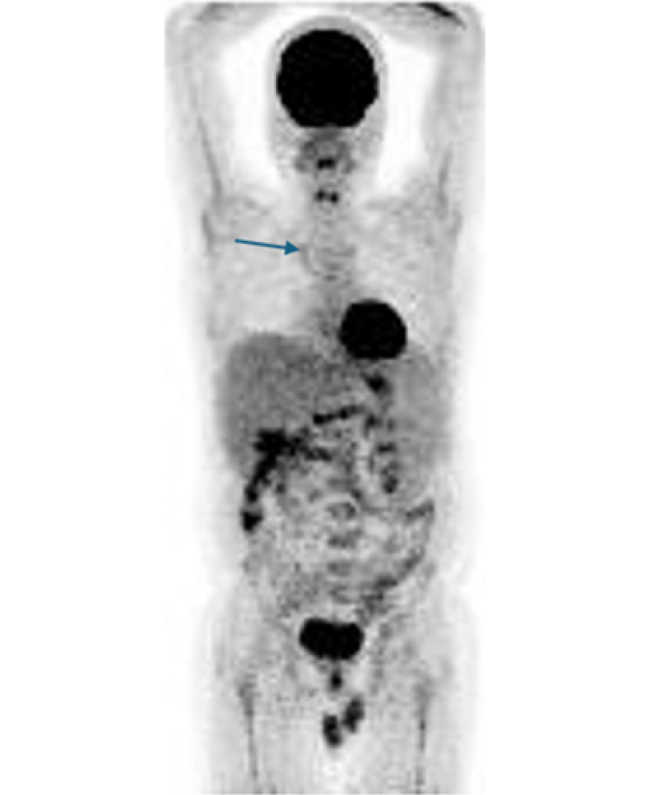

Case description: We present the case of an adult patient with common variable immunodeficiency and interstitial lung disease. He did not receive rituximab due to an adverse reaction and underwent treatment with azathioprine, achieving prolonged remission after treatment discontinuation.